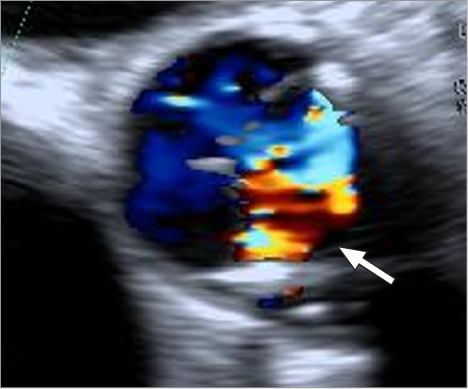

本报告重点介绍了第二代雅培Trifecta Glide技术生物人工心脏瓣膜早期结构性瓣膜恶化并尖端撕裂的病例。一名70岁的男性在30个月前因严重的二尖瓣主动脉瓣狭窄接受了triecta Glide技术瓣膜置换术。经胸超声心动图显示,患者因主动脉瓣严重反流导致急性心力衰竭并呼吸困难,同时出现Trifecta Glide Technology瓣膜尖端撕裂。患者通过紧急重复主动脉瓣置换术成功治疗。

This report highlights a case of early structural valve deterioration with a cusp tear in a second-generation Abbott Trifecta Glide Technology bioprosthetic heart valve. A 70-year-old man had undergone aortic valve replacement with a Trifecta Glide Technology valve 30 months earlier for severe bicuspid aortic valve stenosis. He suddenly developed acute heart failure with dyspnea resulting from severe aortic valve regurgitation, with a cusp tear in the Trifecta Glide Technology valve, as demonstrated by transthoracic echocardiography. The patient was successfully treated with urgent repeat aortic valve replacement.